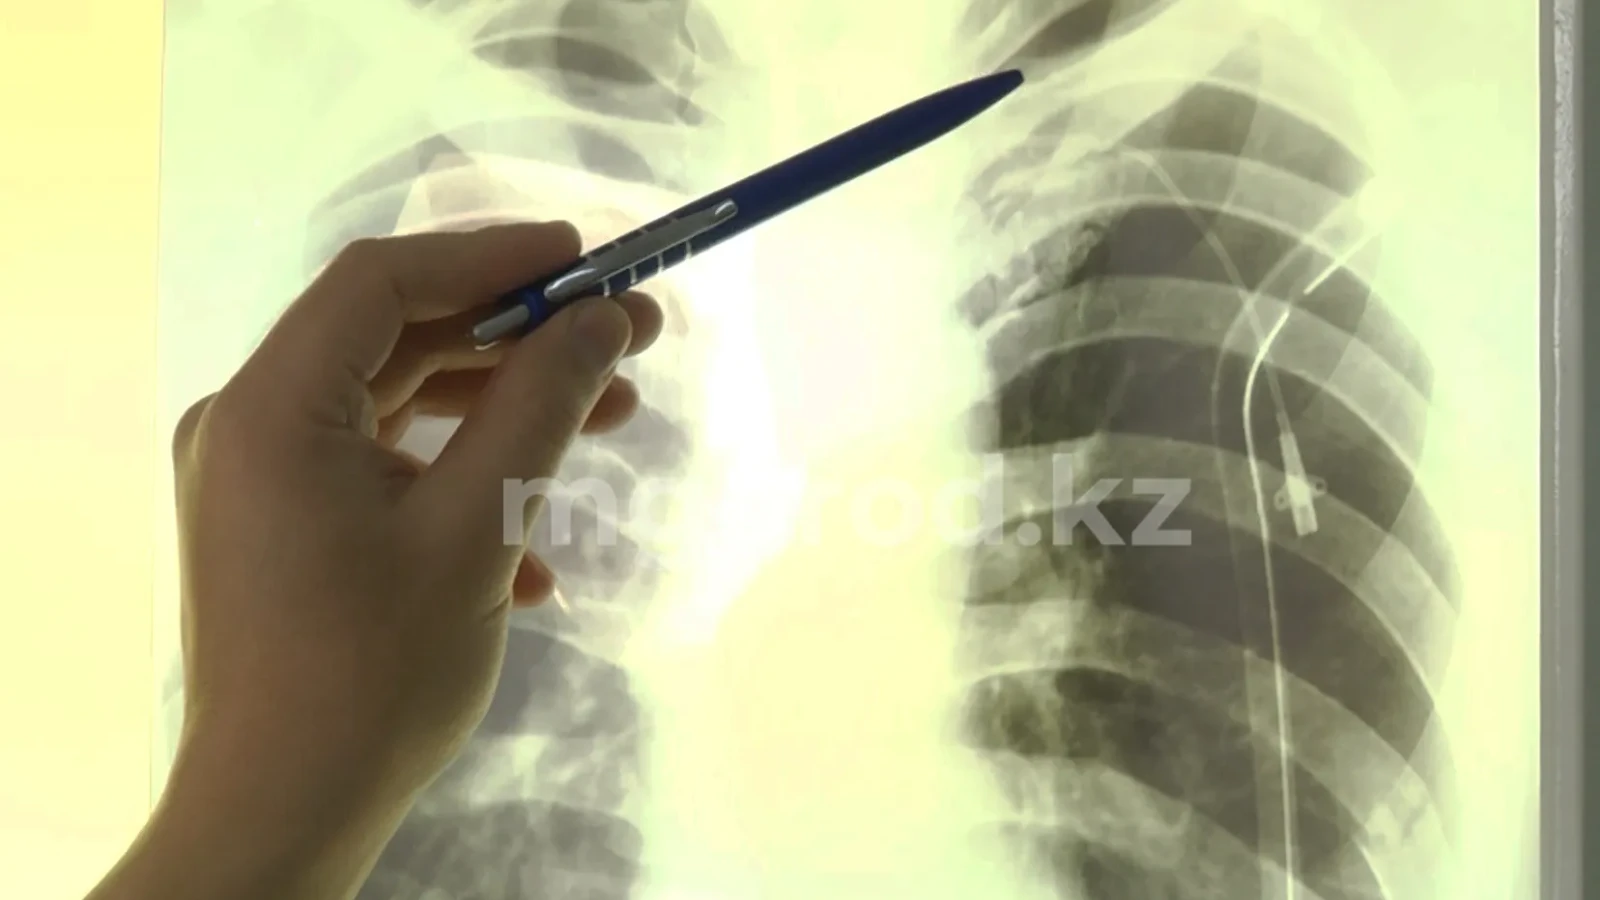

— Первый раз предмет был проглочен 30 декабря, но рентген показал, что внутри его нет. То есть он вышел естественным путем. Затем 23 января подследственный глотает саморез. Его осматривали два хирурга и экстренных показаний к операции не было. Поэтому его отправили в поликлинику, чтобы планово встать на портал и сделать операцию. С тех пор он начал проходить обследования, сдавать анализы, его осматривали профильные специалисты. А сегодня утром его поставили на портал. Все это время за ним наблюдал персонал нашей поликлиники. Я лично осматривала его, никой желтушности, температуры или кровотечения не было, — говорит Жанар Амангельдиевна.